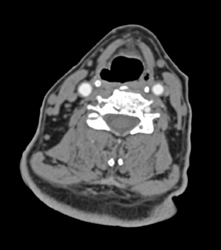

Carotid Artery Stenosis